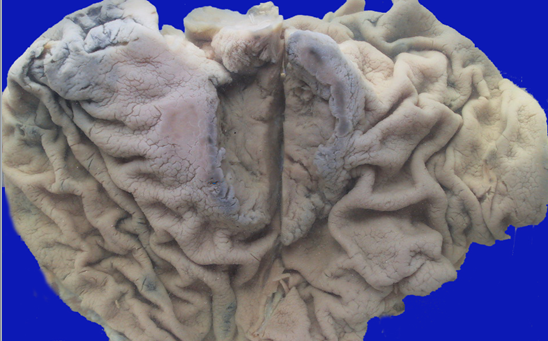

B:弥漫浸润型:即“革囊胃”,癌组织弥漫浸润胃壁各层伴纤维组织增生,使胃腔缩小,皱壁消失,质地变硬,呈皮革状,称之。特征为“厚、硬、小“。